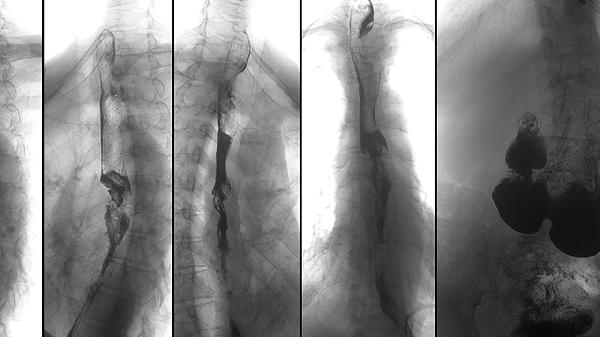

对于骨骺未完全闭合者,重组人生长激素可刺激骨骼纵向生长。需经专业医生评估骨龄后使用,治疗期间需定期监测血糖和甲状腺功能。该方式对特发性矮小症患者效果较显著,但存在关节疼痛、水肿等潜在副作用。